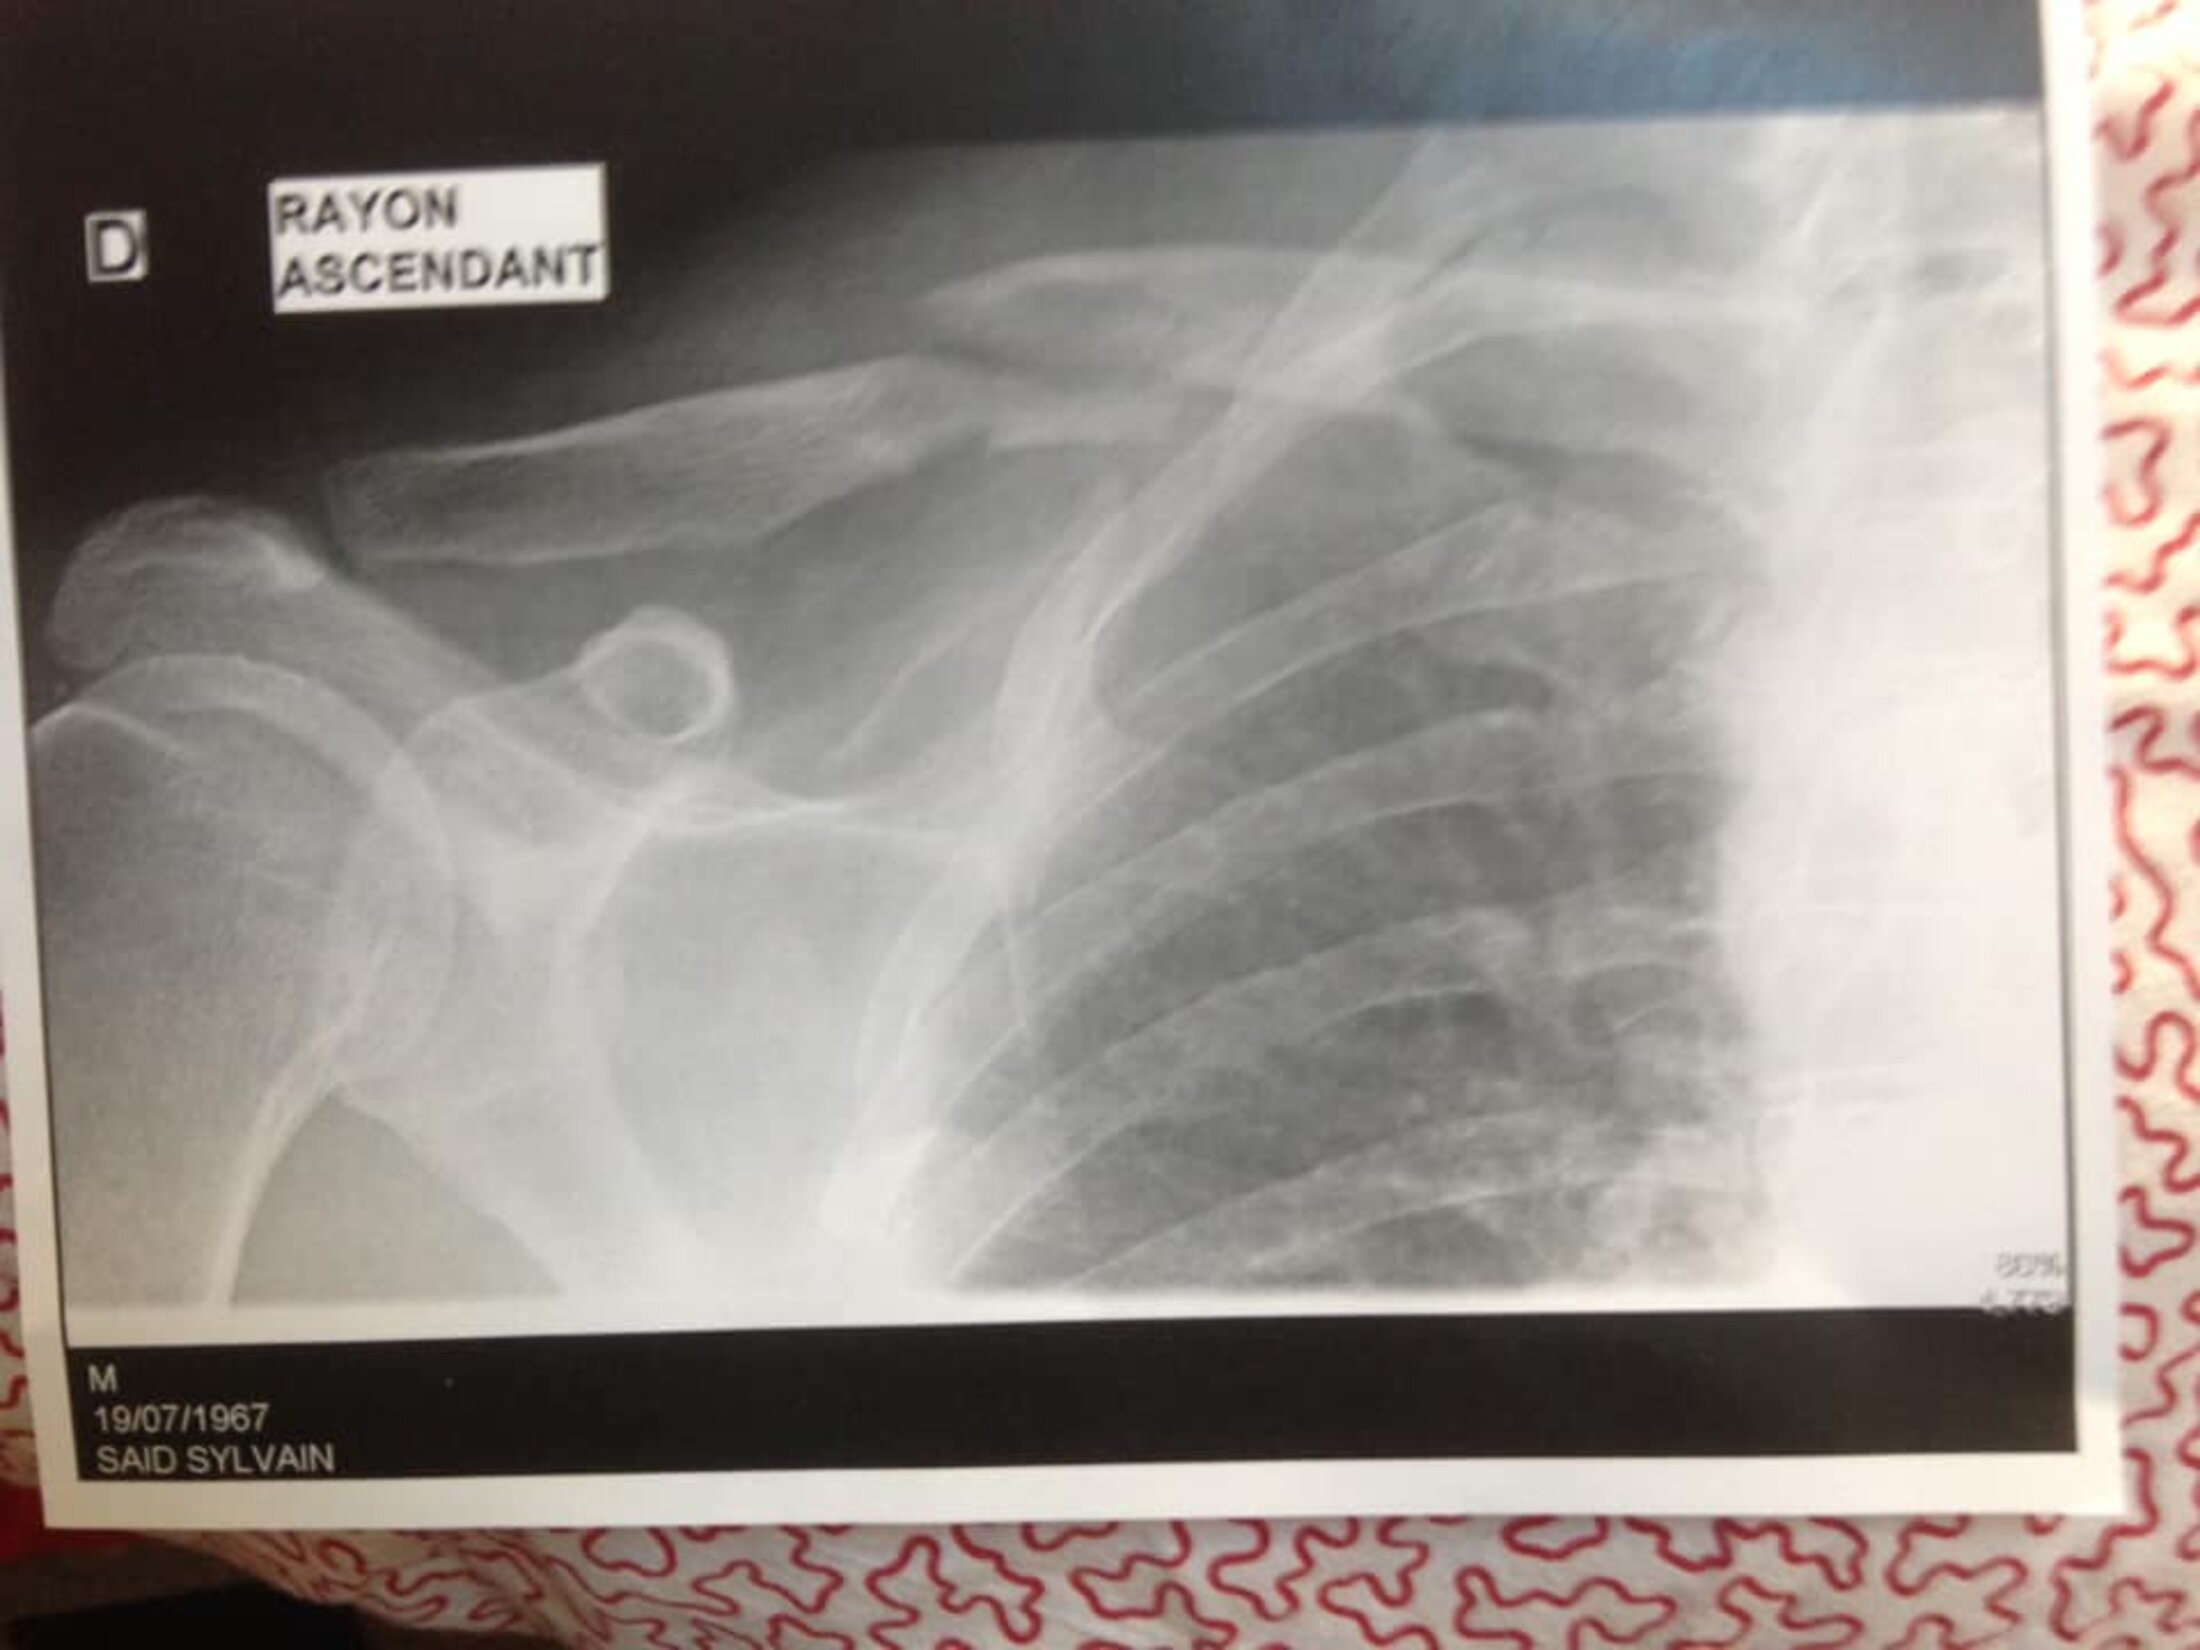

Six jours après le début du confinement, j'me suis vautré en bécane, en allant au turf (service de maladies infectieuses et tropicales). Ma meule pèse 250 kilos et même à 30 km/h, quand tu glisses sur des gravillons à l'entrée d'un rond-point, tu morfles sévère. Clavicule droite pétée en 3 (cf radio).